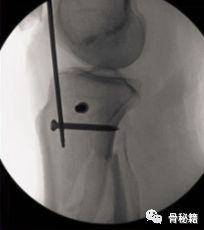

最佳的进针点的位置,关节面的最前缘处,正位位于外侧髁间嵴的内侧。

一个好的进钉点,保证了你的好的开端,要不然越做越难受

以下是两个反面教材,进针点过低,导致了胫骨前后成角,进针点太靠内,导致了近端外翻。